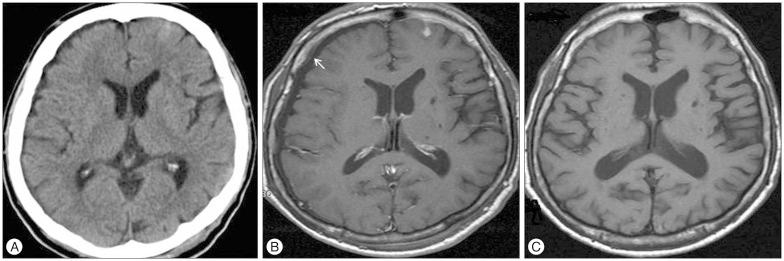

Thirty-one patients suffered from bilateral SDG, whereas 14 had unilateral SDG. Follow-up computed tomography scans revealed regression of SDG in 25 of 45 patients (55.6%), but the remaining 20 patients (44.4%) suffered from transition to CSDH. Eight patients developed bilateral CSDH, and 12 patients developed unilateral CSDH. Hemorrhage-free survival rates were significantly lower in the male and bilateral SDG group (log-rank test; =0.043 and =0.013, respectively). Binary logistic regression analysis revealed male (OR, 7.68; 95% CI 1.18-49.78; =0.033) and bilateral SDG (OR, 8.04; 95% CI 1.41-45.7; =0.019) were significant risk factors for development of CSDH.

31例患者患有双侧SDG,而14例患有单侧SDG。随访计算机断层扫描显示,45例患者中有25例(55.6%)的SDG消退,但其余20例患者(44.4%)转变为CSDH。8例患者发生双侧CSDH,12例患者发生单侧CSDH。男性和双侧SDG组的无出血生存率显著较低(对数秩检验;分别为=0.043和=0.013)。二元逻辑回归分析显示,男性(比值比,7.68;95%置信区间1.18-49.78;=0.033)和双侧SDG(比值比,8.04;95%置信区间1.41-45.7;=0.019)是CSDH发生的显著危险因素。